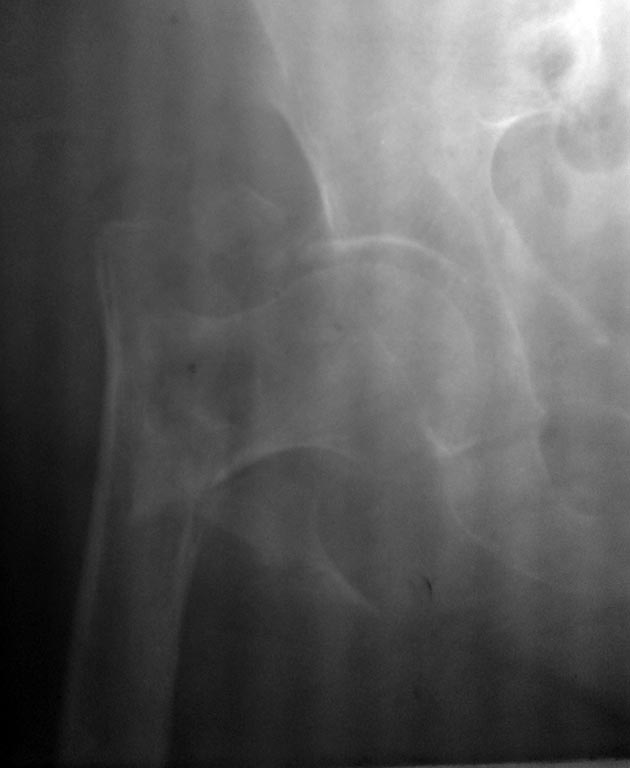

Пример перелома, который можно сравнить с Вашим